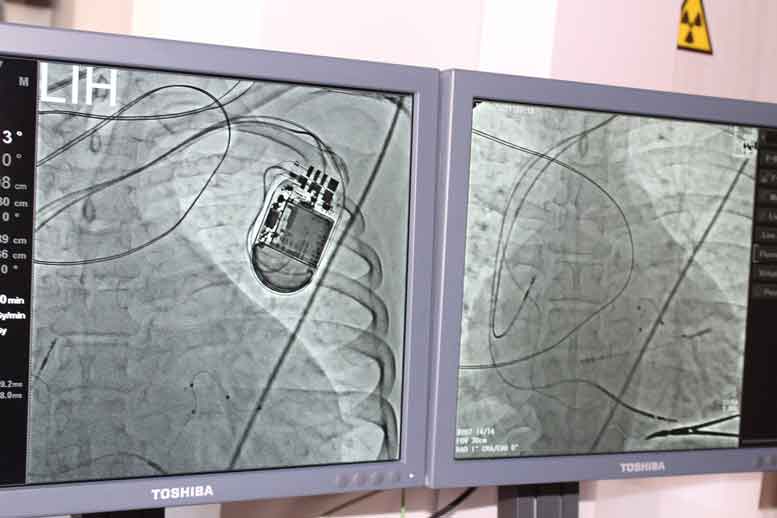

Вперше у Ковельському МТМО провели імплантацію одного з найскладніших приладів, що рятує життя людині при раптовій зупинці серця.

Наші лікарі успішно провели операцію зі встановлення трьохкамерного кардіостимулятора з функцією дефібриляції пацієнту, який багато років страждає на дилатаційну кардіоміопатію. Він потребує трансплантації серця і перебуває у листі очікування в Ковельському МТМО.

Тож відтепер у грудях 53-річного лучанина працює своєрідна «бригада швидкої допомоги». Прилад в режимі 24/7 контролює ритм серцевих скорочень та знімає напади загрозливих для життя аритмій. До операції чоловік міг пройти без задишки лише 250 метрів. Зараз він легко долає 560 метрів за 6 хвилин‍. Чоловік ще деякий час перебуватиме під наглядом лікарів, а потім зможе повернутися до активного соціального життя.